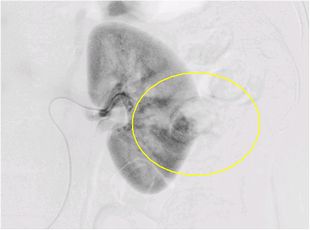

当院では、高精度画像診断によって、より早期の段階で腎がんを診断することに努めています。小さな腎腫瘍においては、しばしば良性腫瘍とがんの鑑別が難しいことがありますので、腹部超音波検査、CT検査MRI検査、また血管造影検査を組み合わせて、総合的に診断を行います。

血管造影検査